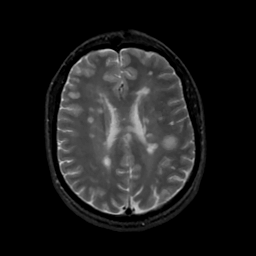

MR Study #16, June 23, 1991 -- Slice #32